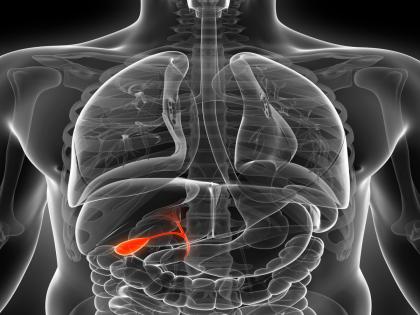

पित्ताशयाचे कार्य काय?

पित्ताशय हा यकृताच्या मागे व खालच्या बाजूला असलेला एक छोटा पिशवीसारखा अवयव आहे. पित्ताशयाचे मुख्य काम पित्त साठवणे व त्याचा निचरा करणे होय. यामुळे आहारातील चरबीचे पचन होण्यास मदत होते.